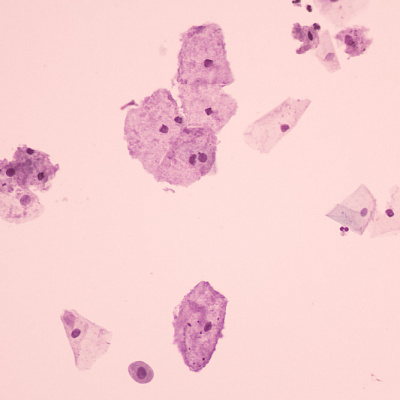

Врачи выделяют три степени патологии. Они определяются по составу микрофлоры при микроскопическом исследовании:

- Компенсированный. Полезных лактобактерий стало меньше, но вредные микробы пока не размножились слишком сильно. Однако риск их роста повышен.

- Субкомпенсированный. Лактобактерий уже мало, а условно-патогенных бактерий становится больше, чем в норме. Это приводит к появлению первых неприятных симптомов.

- Декомпенсированный. Полезные бактерии почти полностью исчезают, а вредные активно размножаются. На этом этапе женщина испытывает выраженный дискомфорт: появляются неприятные выделения, зуд, жжение, неприятный запах.

- Мазок на флору. Покажет, какие бактерии есть, есть ли воспаление и нарушен ли баланс.